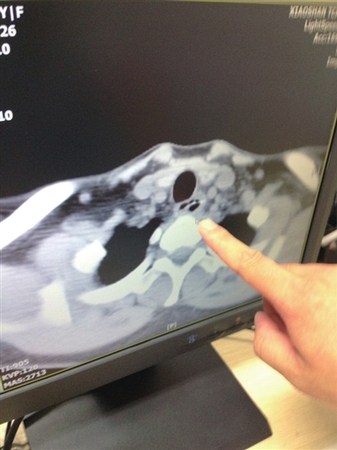

两年来,家住青白江的28岁女子杨女士肛周反复发炎、流脓,可算是吃了不少苦头。一开始,杨女士以为是普通的肛瘘病症,只是通过简单的消炎药处理,但始终未见好转。前不久,不堪忍受病痛折磨的她,终于鼓起勇气到青白江区人民医院做了手术。令她想不到的是,让其“坐立不安”的“罪魁”,竟是一根6厘米长的粗鱼刺,卡在距肛门约10厘米处的狭小直肠腔隙中!

两年前,杨女士发现自己肛周出现反复发炎、流脓现象,但因患病部位隐私,不便就医,羞涩的杨女士只是在药店或诊所买了一些消炎药使用。杨女士告诉医生,用药后情况倒是有所好转,可是却始终治标不治本,炎症继续复发,久治不愈,让她苦不堪言。

后来,杨女士鼓起勇气来到医院就医。“医生,我肛周反复发炎、流脓,持续了快两年?!备菅钆康母髦种⒆疵枋?,医生一开始的诊断也跟普通的肛瘘病症相同,开药后进行治疗。但是,杨女士在用药后炎症仍然比较反复。